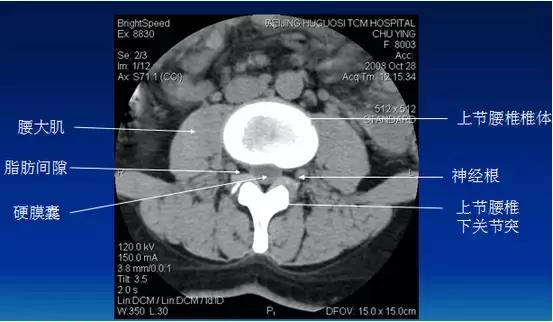

常规腰椎CT扫描层面

常规腰椎CT扫描L3-S1段,分为

(1)椎体层面(骨窗):视察椎体、附件骨质。

(2)椎间盘层面(软组织窗):视察椎间盘、硬膜囊、神经根、韧带等软组织。